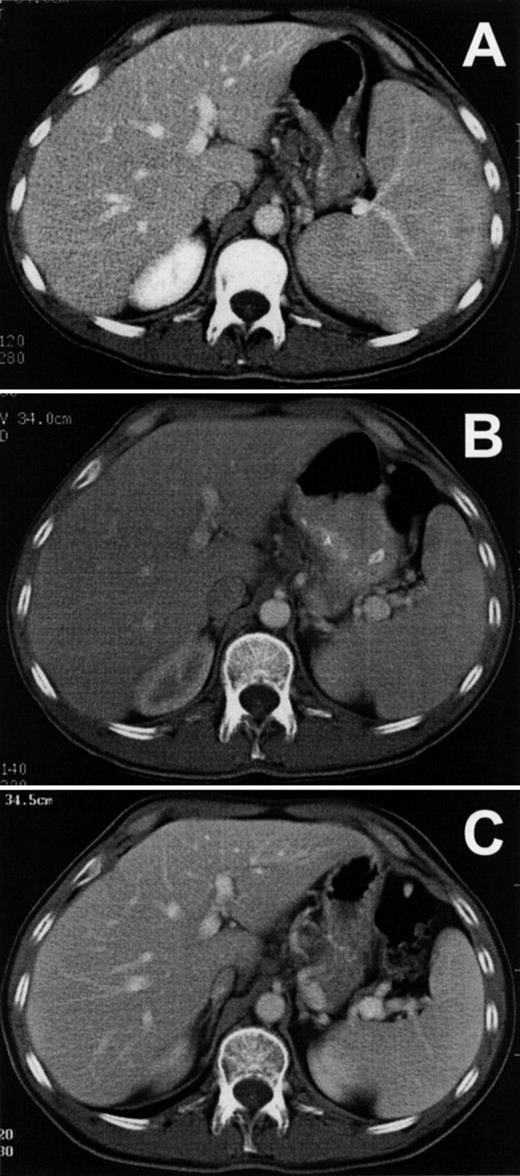

Figure 3A shows the patient’s splenomegaly in axial section before treatment with LMB-2. The cranial-caudal diameter was 16 cm, and after 1 cycle of LMB-2 decreased to a normal size of 11 cm by day 31 (Fig 3B). The spleen size was 9 cm after cycle 2 and showed no evidence of progression during 5 months off treatment, as shown in Fig 3C. The patient had abnormally enlarged precarinal adenopathy (up to 1.6 cm) before LMB-2, which also resolved after the first cycle. The pretreatment bone marrow biopsy was infiltrated with HCL cells, and liquid marrow could not be aspirated. The marrow biopsy by day 8 was no longer positive for HCL and was negative on day 206, showing hypocellularity with adequate normal hematopoietic precursors. However, the marrow aspirate on day 206, which could be obtained for the first time since the patient’s diagnosis, contained 0.15% malignant cells by FACS. Thus, malignant cells outside blood vessels responded to LMB-2, but minimal residual HCL could be detected by FACS in the bone marrow aspirate.

Reduction of spleen size in HCL. Axial sections are shown from computed tomography performed on patient no. 1 before (A) and after (B) the first cycle of LMB-2 and then on day 175 of the second cycle (C).